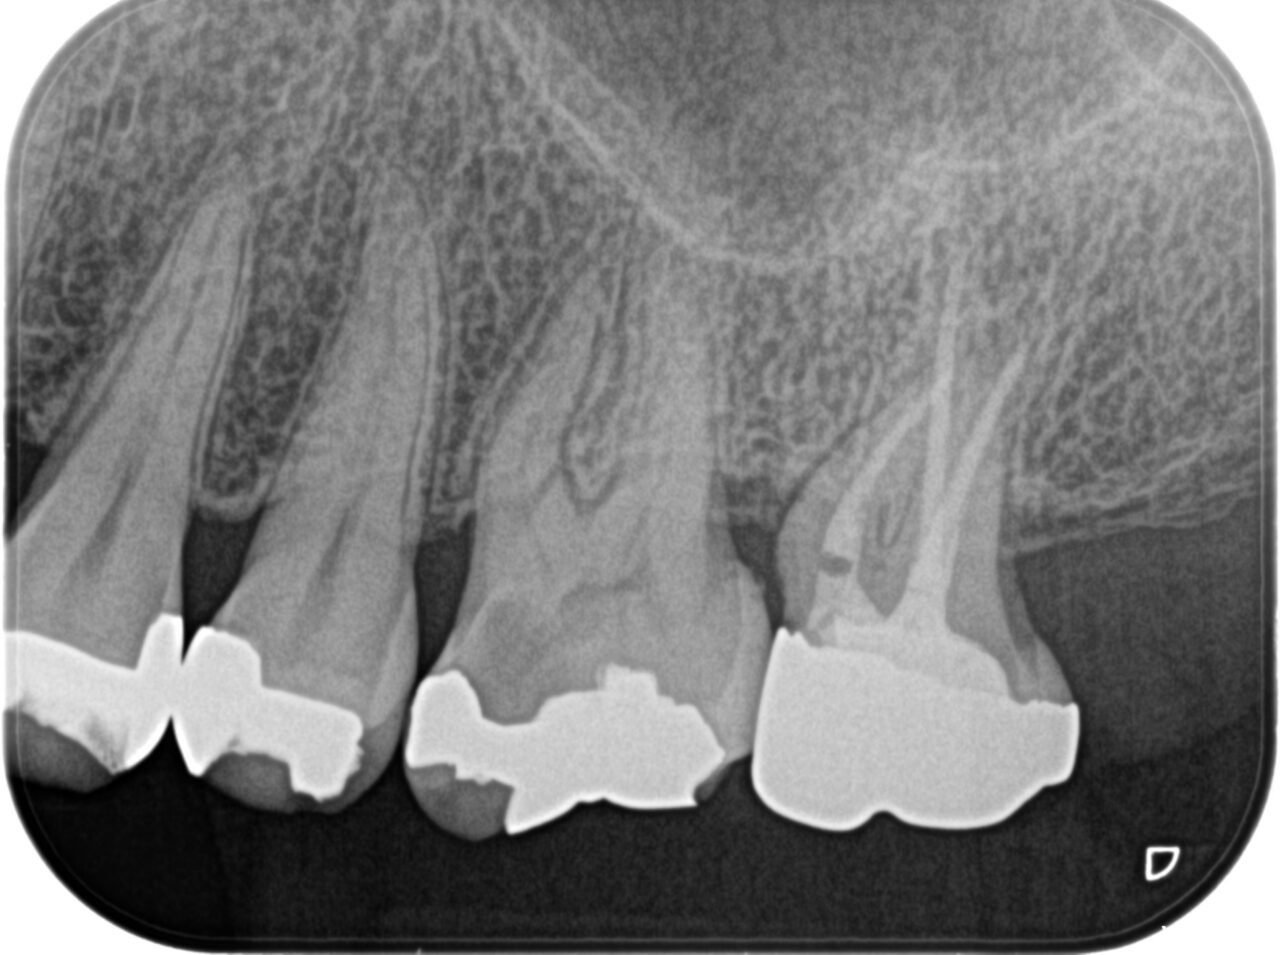

症例1

Before

After

年齢/性別 | 40代/女性 |

|---|---|

主訴 | 根の先の膿を治してほしい マイクロスコープを使用して根管治療をしてほしい |

治療内容 | ラバーダム防湿、マイクロスコープを使用した精密な根管治療 |

治療回数 | 根管治療1回で完了 |

治療費 | 根管治療+被せ物 約25万円 |

注意点 | この根管には偽根管と本来の根管とは違う、人為的な偽の根管が存在。本来の根管の中の感染源を除去するのが困難な症例。ニッケルチタンファイルを使用しプレカーブを付与して本来の根管へアプローチした。近心根管にMB2がCTで確認できた。しかし、非常に狭窄している。通常の器具では未治療根管となるだろう。 |